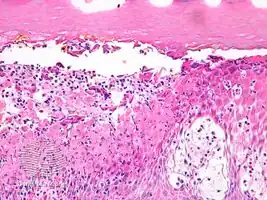

Infected keratocytes in skin swell and die.[2] The stain Lendrum’s phloxine tartazine, may be used to identify farmyard pox inclusion bodies.[2] Other tests include culture, fluorescent antibody test and electron microscopy.[2]

Cowpox, horsepox and smallpox may look similar and the histology may appear the same.[2]